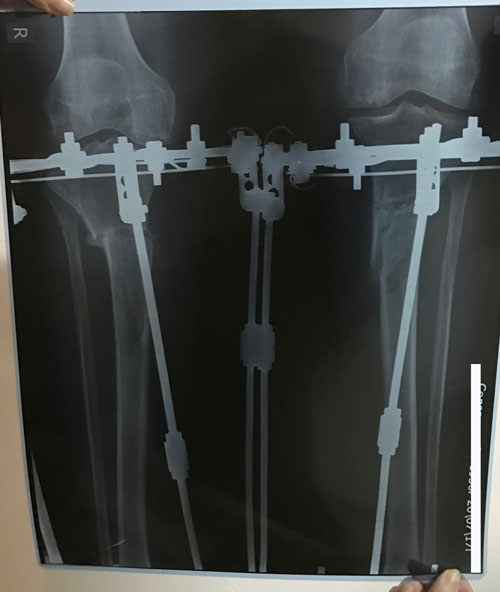

Исходник - 60 лет.

Дата операции 23.05.2017г.

Рентген и ото ножек в 60 дней.

Срастаетесь, как молодые девчонки

Дата снятия аппаратов 16.10.2017г.

Срок лечения 142 дня.